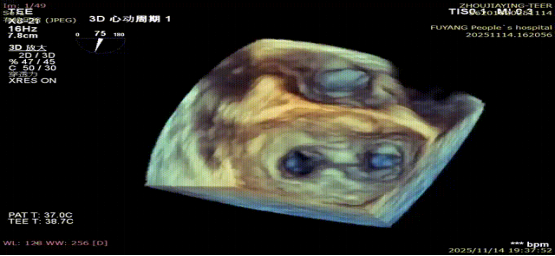

手术当日,在全身麻醉及TEE全程导航下,陈玺全副主任团队凭借丰富的临床经验与精湛操作技巧,顺利完成房间隔穿刺、瓣叶精准定位等关键步骤。针对患者二尖瓣A2/P2 区域反流靶点,团队精准夹合瓣叶,经X-plane技术与三维超声反复确认夹持质量后,成功释放一枚MitraClip XTR夹子。术后即时评估显示,患者二尖瓣反流由术前3 +重度降至轻度,平均跨瓣压仅3mmHg,手术达到预期效果,全程无并发症发生。

术后第二天,患者顺利返回普通病房,并可自主下床活动,进食、睡眠等生活状态逐步恢复正常。术后超声显示残余轻度反流,肺静脉血流恢复正常,患者症状较前明显改善,活动耐量提升,生活质量显著提高。术后1周,患者各项生命体征平稳,顺利康复出院。“没想到不用开胸就解决了这个大毛病,还能恢复这么快、这么好!”出院当天,患者及家属对手术效果和就医体验给予高度评价,并衷心感谢医护人员的专业诊疗和无微不至的关怀照护。